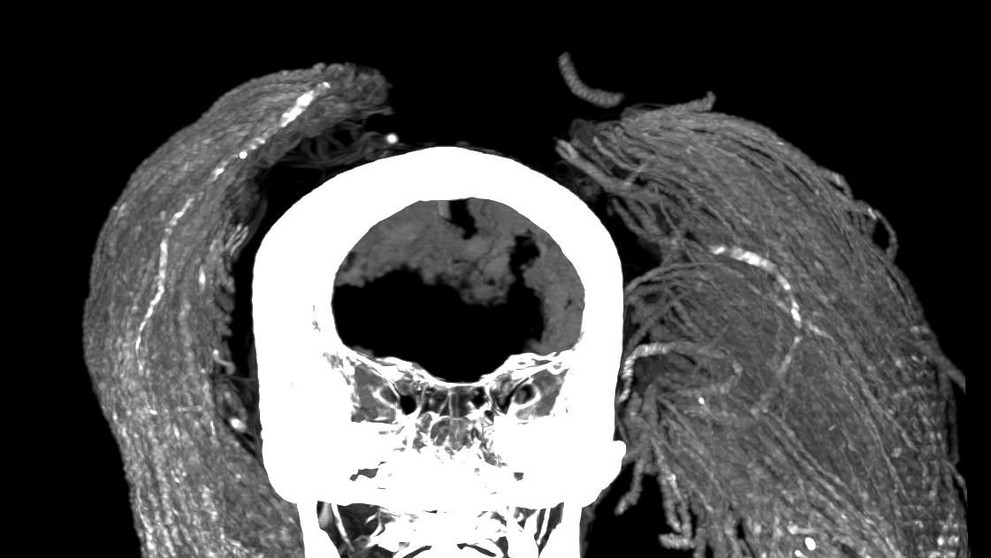

​Profesorka Saleem a ďalšia spoluautorka štúdie Dr Samia El-Merghaniová v časopise Frontiers in Medicine uvádzajú, že ich hlavným pracovným nástrojom bola počítačová tomografioa (CT).

Pri virtuálnej pitve múmie využili aj technológiu röntgenovej difrakcie, vďaka ktorej mohli preskúmať zloženie kože, vlasov a dlhej čiernej parochne. Prvé, čo si všimli bolo, že múmia je vzhľadom na svoj vek dobre zachovaná.

Žena počas života merala 155 cm a v čase úmrtia mala 48 rokov. Laboratórne testy odhalili, že trpela artritídou, ktorá sa jej rozšírila aj do chrbtice. Čo je však pre výskum najpodstatnejšie, vedci nenašli žiadne známky balzamovacieho rezu a všetky orgány boli stále vo vnútri múmie.